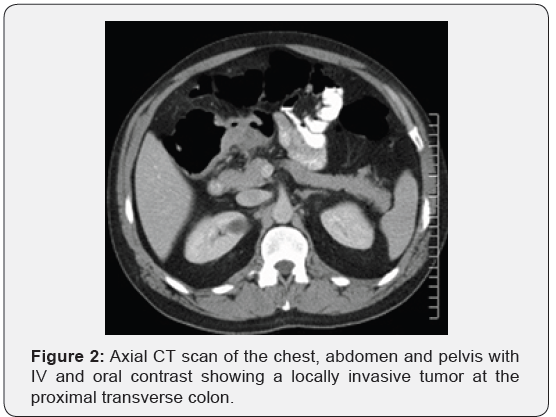

Immunohistochemistry revealed a strong positivity for AE1/ AE3 and Cytokeratin 20 (CK20), and PASD stained for mucin, but the staining for Cytokeratin 7 (CK7), p63, and TTF-1 was negative. The findings suggested a likely primary colorectal origin. He underwent an urgent OGD and full colonoscopy. OGD revealed a normal esophageal mucosa and mild gastritis which tested negative for H. pylori. Full colonoscopy detected a partially-obstructing circumferential mass at the proximal transverse colon near the hepatic flexure. The biopsy report from this colonic mass confirmed an invasive poorly-differentiated colonic adenocarcinoma and the findings were almost identical to the left supraclavicular node’s biopsy. The patient had a computed tomography (CT) scan of the chest, abdomen and pelvis which depicted a locally advanced proximal transverse colon tumor spreading well beyond the serosa posteriorly with local infiltration of pericolic fat and regional lymphadenopathy Figure 2-A. There was a significant metastasis in the para-aortic nodes Figure 2-B, anterior mediastinal nodes Figure 2-C and left supraclavicular nodes Figure 2-D. No evidence of hepatic, pulmonary or bony metastasis noted. Carcinoembryonic antigen (CEA) level was above the normal (22 ng/ml, normal reference <3.5 ng/ml). Alpha-fetoprotein (AFP) level was within the normal ranges.